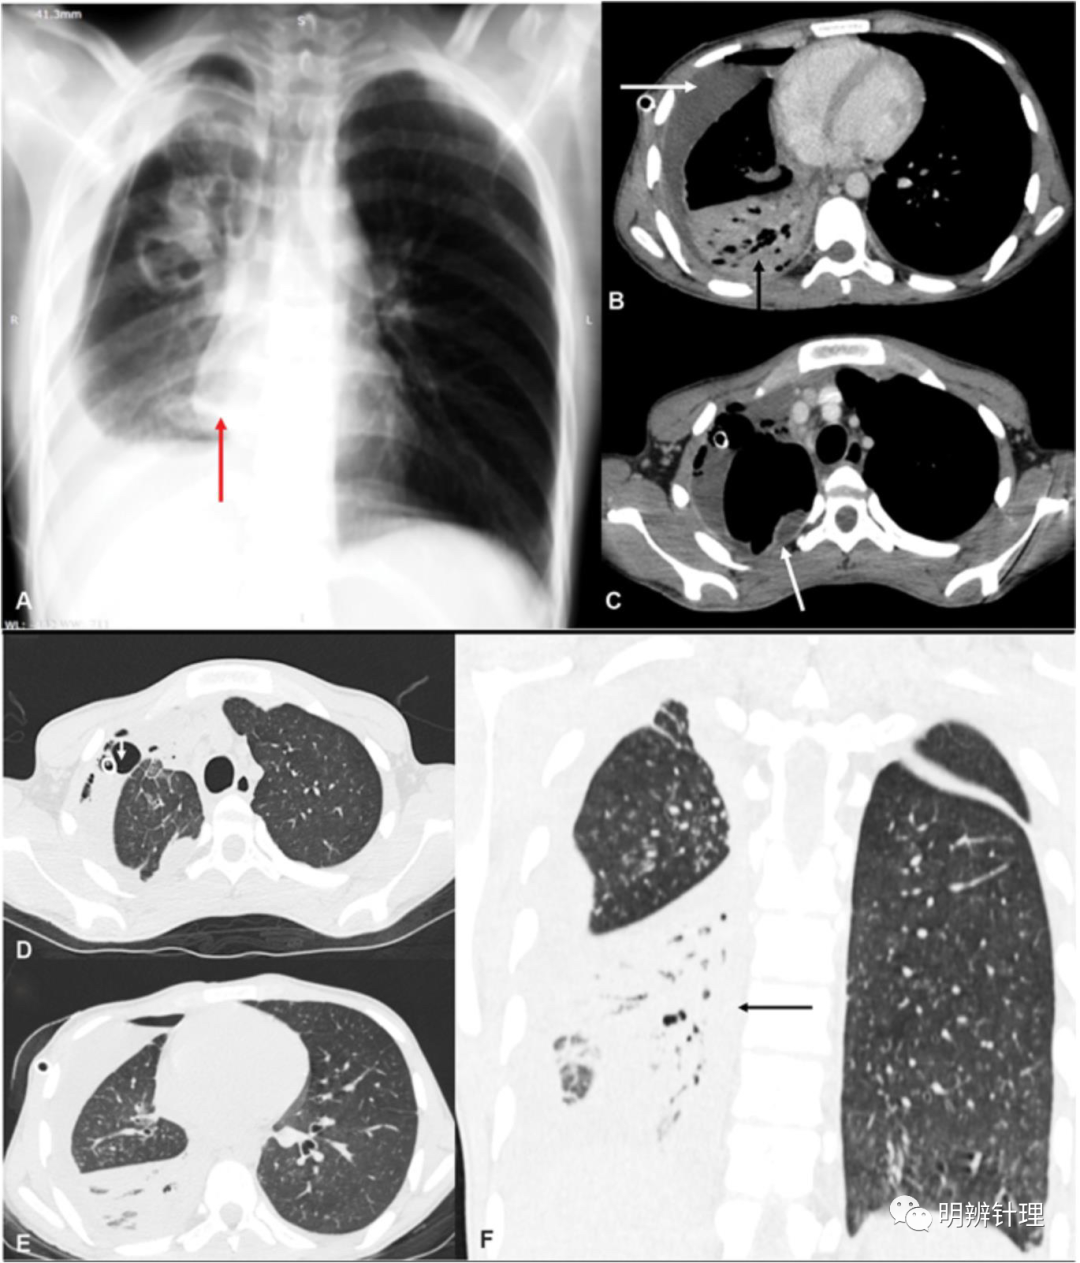

男性,18 岁,发烧、咳嗽和胸痛一周,糖尿病病史。胸片 ( A ) 显示右侧心后部密度影(红色箭头)和右侧液气胸并有引流管。对比增强计算机断层扫描 ( B–F ) 显示右侧脓气胸(白色箭头)( B ),右下叶实变伴气管支气管征(黑色箭头)( B ),左侧后基底段早期受累(黑色箭头)( F)。

诊断结果:血培养和痰培养:葡萄球菌